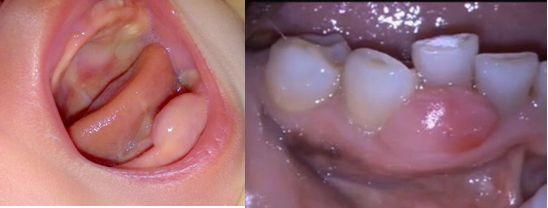

Se denominan ránula cuando se presentan en el piso de la boca y épulis cuando aparecen en las encías.

Ránula oranita”, es el término dado a mucoceles, localizados dentro del piso de la boca,es un quiste benigno, mucoso.

Esta variedad de mucocele es típicamente más grande y causada por la extravasación de mucina de la glándula sublingual, o menos comúnmente las glándulas submandibulares conducto salival o, glándulas menores del el piso de la boca.En niños, el diagnóstico diferencial principal incluye malformaciones vasculares como linfagiomas, abscesos infecciosos, y tumores de tejido blandos.

La histología es similar a mucoceles localizados en otro lugar en la cavidad oral. Clínicamente, las ránulas aparecen como una tumoración azul, son hinchazones fluctuantes en el suelo de la boca, laterales a la línea media.

Épulis

Épulis congénito o tumor gingival de células granulares, es un raro tumor benigno del tejido blando que aparece exclusivamente en recién nacidos. Las mujeres son más afectadas que los hombres (8:1 a 10:1). Estos suelen presentes al nacer,  como una masa pediculada en la mucosa alveolar mandibular premaxilar o con nódulos solitarios o múltiples.

El épulis se encuentra en la cresta maxilar, principalmente como tumores únicos, y rara vez como tumores múltiples